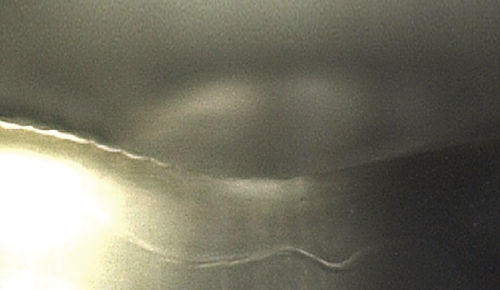

固体(アイス・ニードリング) VS 液体浸透比較

個体(アイス・ニードリング)

氷の粒子は衝突時に変形されずに表面を通り抜けます。これにより、薬剤を皮内へ浸透させることが可能です。

液体

液体は衝突時に変形されて表面から飛び跳ねます。よって、薬剤が液状で皮膚表面に残るようになります。

アイス・ニードリングは、表皮と真皮の境界にあたる表皮真皮接合部(DEJ)を正確にターゲットとしています。ターゲットクールを用いて希望の薬剤を導入することで、薬剤成分が表皮から真皮にかけて作用し、より効率的かつ素早い効果を実感いただけます。